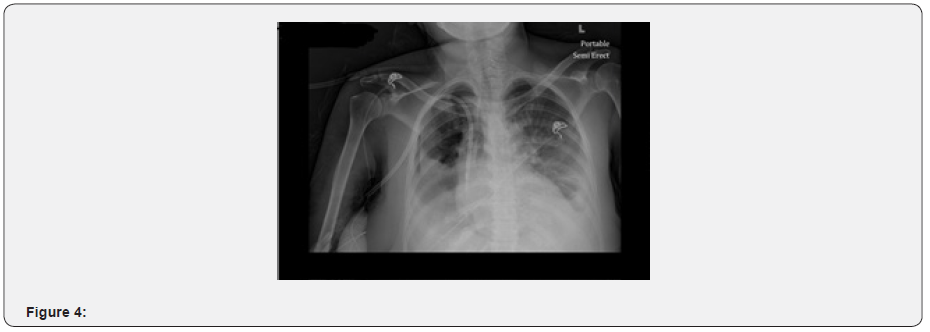

X ray on the following was now significant for a right hydro-pneumothorax in the same location. Effusion the left still unchanged from that on the left (Figure 4). The patient continued to be at her baseline health status and had no active complains from the effusions. As the patient remained stable, she was discharged to the nursing home with regular outpatient hemodialysis sessions and aggressive treatment of her hypertensive heart disease with carvedilol, amlodipine, hydralazine and lisinopril (Figure 5).